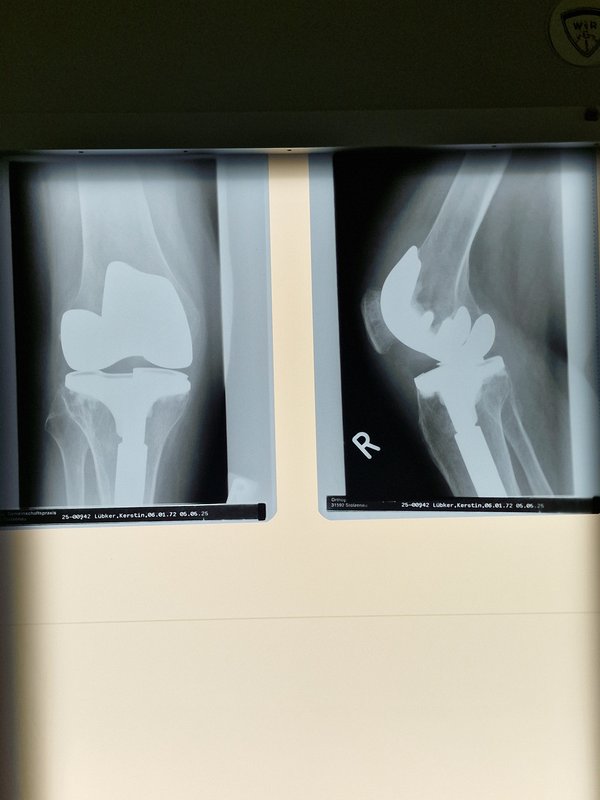

Bild

Hab was gefunden 😃

Hast ein sehr schönes Knie 🤣.